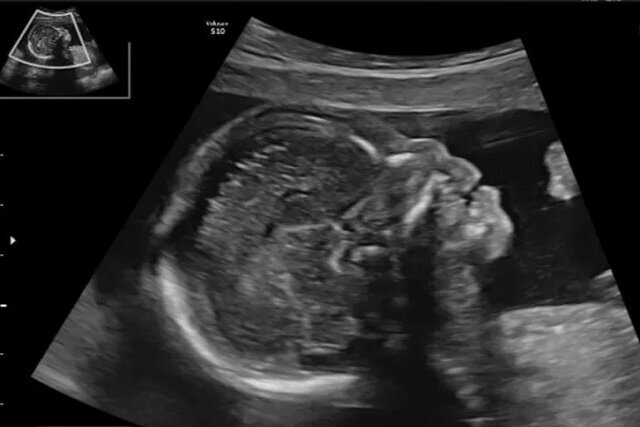

در سال‌های اخیر پیشرفت‌های تصویربرداری در بارداری به پزشکان امکان داده تا زودتر از گذشته ناهنجاری‌های جنینی را تشخیص دهند. یکی از شاخص‌هایی که در این مسیر اهمیت زیادی یافته، وضعیت استخوان بینی جنین است که می‌تواند نشانه‌ای از برخی اختلالات ژنتیکی باشد.

شفاآنلاین »سلامت» اختلالات کروموزومی مانند سندرم داون از شایع‌ترین ناهنجاری‌های ژنتیکی در میان نوزادان هستند. این وضعیت در حدود یک مورد از هر ۸۰۰ تولد زنده دیده می‌شود و به دلیل تأثیر آن بر رشد ذهنی و جسمی کودک، شناسایی زودهنگام اهمیت زیادی دارد. از سال‌ها پیش، پزشکان متوجه شدند که نبود یا کوچکی استخوان بینی جنین می‌تواند یکی از نشانه‌های احتمالی سندرم داون باشد. با این حال، این یافته در جمعیت‌های مختلف، از نظر نژادی و جغرافیایی تفاوت‌هایی دارد و همین مسئله ضرورت انجام مطالعات اختصاصی برای هر منطقه را نشان می‌دهد.

به گزارش شفاآنلاین در ایران نیز با توجه به تنوع قومی و ویژگی‌های ژنتیکی گوناگون، اندازه و رشد استخوان بینی ممکن است با میانگین‌های جهانی تفاوت داشته باشد. به همین دلیل بررسی وضعیت این استخوان در جنین‌های ایرانی در سه‌ماهه‌های مختلف بارداری می‌تواند به بهبود غربالگری و کاهش نتایج اشتباه در تشخیص کمک کند. اهمیت این بررسی زمانی دوچندان می‌شود که بدانیم سونوگرافی یکی از کم‌خطرترین و در دسترس‌ترین ابزارهای بررسی سلامت جنین است.